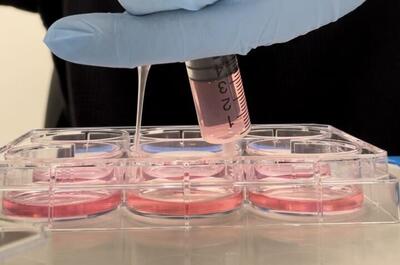

پرورش سلولهای مغزی در فضا راهکاری برای درمان بیماریهای عصبی

پرورش سلولهای مغز در محیط ریزگرانش فضا فواید خاصی دارد.